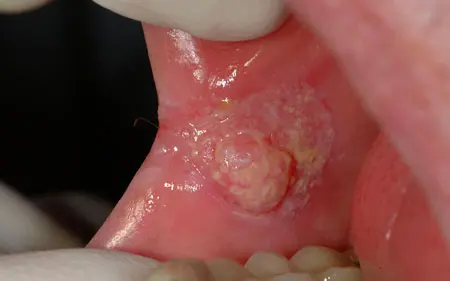

oral cancer inside a cheek

Oral cancer on inside of the cheek.

• Any sore that doesn’t heal

• Red, white, or black patch on the soft areas of your mouth

• Spot that bleeds easily when touched

• Lump or hard spot, usually on your tongue edge